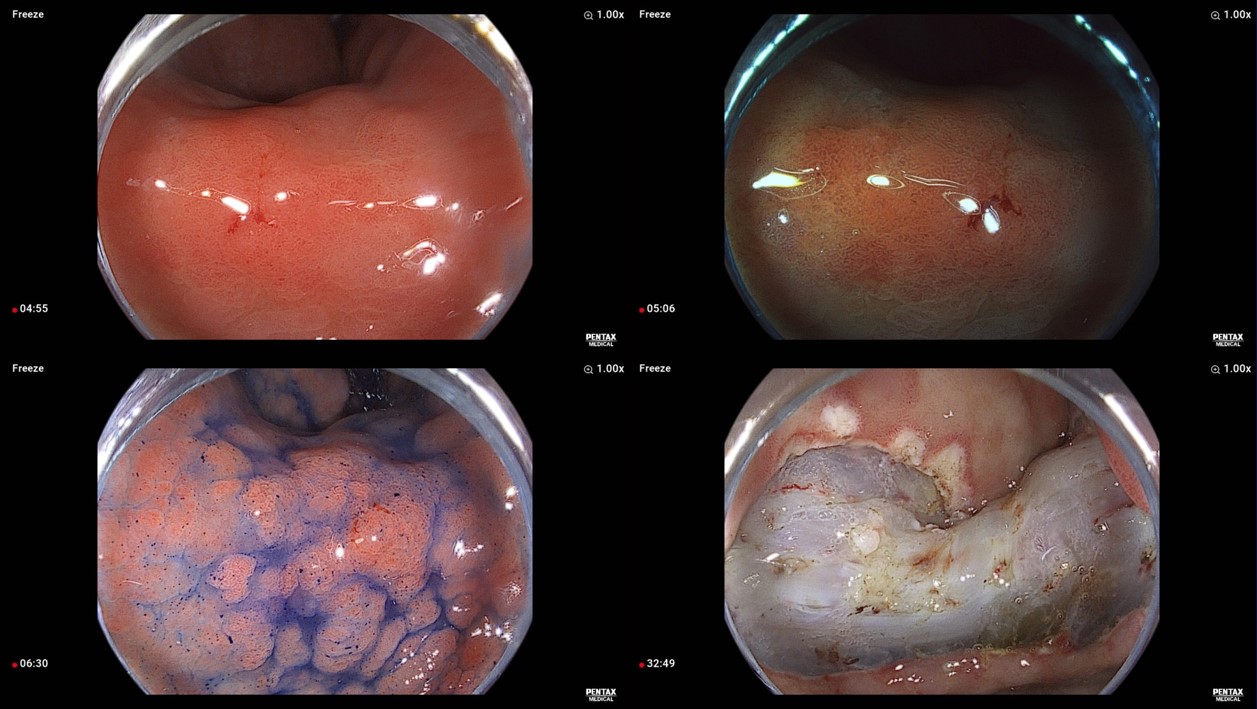

À§ ESD ÈÄ ³»½Ã°æ ¼Ò°ß